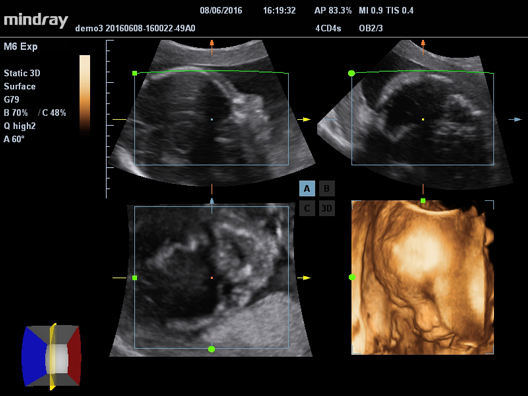

УЗ-сканер Mindray М6 exp представляет собой полнофункциональную портативную, размером с ноутбук, систему цветной допплерографии. Аппарат обеспечивает безупречную визуализацию в формате 2D. Оснащенная специализированными технологиями система М6 exp является оптимальным вариантом для применения.

Галерея изображений